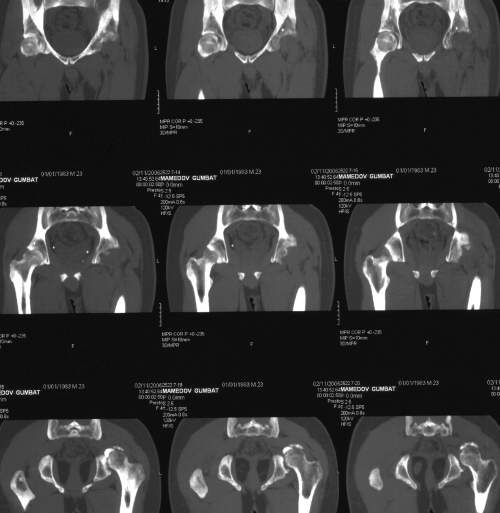

важаемые коллеги,пациент 23 лет (вес 75 кг), обратился к нам по поводу боли в тазобедренном суставе при ходьбе, нестабильность в нем при нагрузке. Ходит с тростью. 8 мес. назад попал в ДТП (никаких медицинских документов у него нет). Стоит ли открываться и вправлять вывих или сразу делать бесцементное тотальное эндопротезирование? С уважением, А. В. Вакуленко Клиника эндопротезирования суставов, г. ДонецкDear All, male patient 23 y.o., body weight 75 kg. Had RTA 8 months ago (medical records unavailable). Now has pain on motion in his left hip. On weight-bearing hip is unstable (patient use cane while walking). Keeping in mind his age, is it worth to perform open reduction? Or just do uncemented THR? Any comments are very welcome.

After 8 months, the hip will not easily come down into the acetabulum. It also appears to me that there is an impression fracture of the head of femur.

у нас есть несколько пациентов с похожей ситуацией после

открытых вправлений в приблизительно такие же сроки, часть из них

устраивает качество жизни, несмотря на явления аваскулярного

некроза и коксартроза (человека 4). Конечно все закончится

эндопротезированием рано или поздно, но пока ходят.

Здравствуйте. Позвольте поучаствовать в обсуждении. Поскольку пациент в течение 8 месяцев не получил адекватного лечения (видимо и по своей вине тоже), а также учитывая удовлетворительное состояние головки бедра(по данным КТ), есть смысл выполнить открытое вправление головки бедра с возможной фиксацией фрагмента заднего края пластиной. Далее начать восстановление функции сустава, дозированную нагрузку. Возможно молодой возраст пациента поможет ему отдалить время эндопротезирования. Желаю успехов.